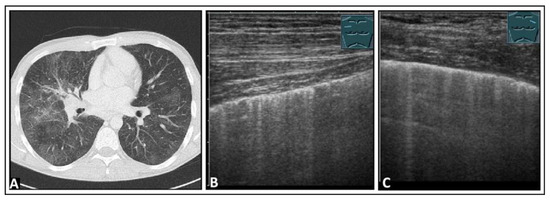

4. Pulmonary Edema and Acute Respiratory Distress Syndrome